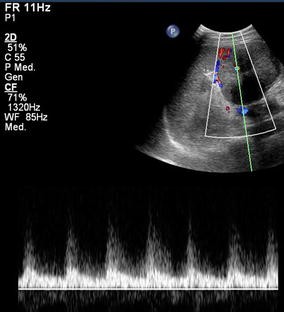

Fig. 1